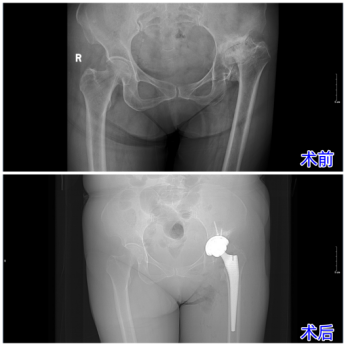

破解数十年髋疾难题,济南南郊医院骨科成功为复杂扁平髋患者实施关节置换术

近日,济南南郊医院骨科杨学良主任团队成功为一位66岁复杂髋关节疾病患者实施了髋关节置换术。